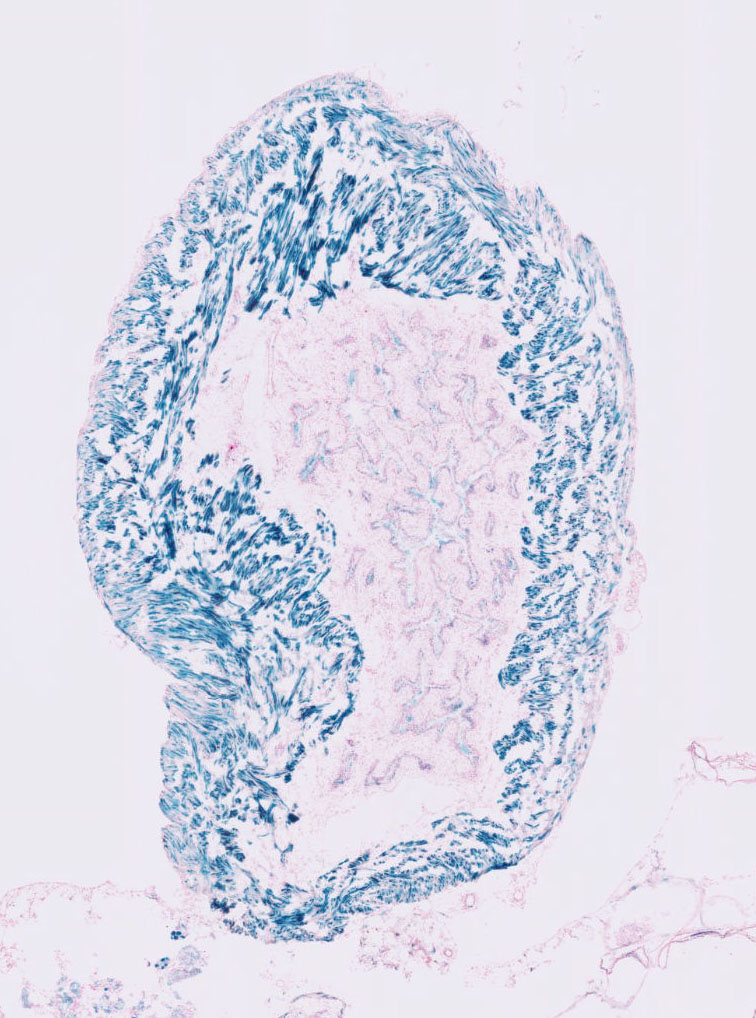

Images

Drag images to compare to others or to data in the table below. Drag corners to resize images for more detail.

Recombinase Activity